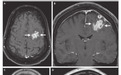

白细胞计数升高,MRI如图。

患者老年女性,急性起病,有意识水平下降,既往重症肌无力病史,结合WBC升高、核磁所示不规则环形强化及周围大水肿带,优先考虑脑脓肿,需完善腰穿和CSF病原学检查。因MG可合并纵膈肿瘤,需鉴别转移瘤。

结合影像学表现,高度怀疑是淋巴瘤,进行了开颅活检,术中冰冻切片并么有提示炎症,也提示有恶性浸润,考虑淋巴瘤,取了组织送病检,没有取额外组织做微生物检测。

术后,尽管接受了糖皮质激素治疗,患者的神经系统状况仍持续恶化,术后第一天,重复头部 MRI 检查显示病情进展,水肿加重。